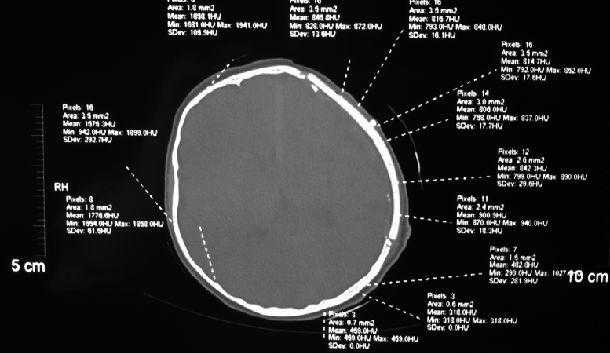

清华仿生骨植入后,在人颅骨缺损处成功生长中:

其他图片:看图请注意,清华大学人工骨(仿生骨)材料与患者自身的颅骨相比较,具有“等厚”,“密度相当”,“美容塑形优秀”等突出优点: